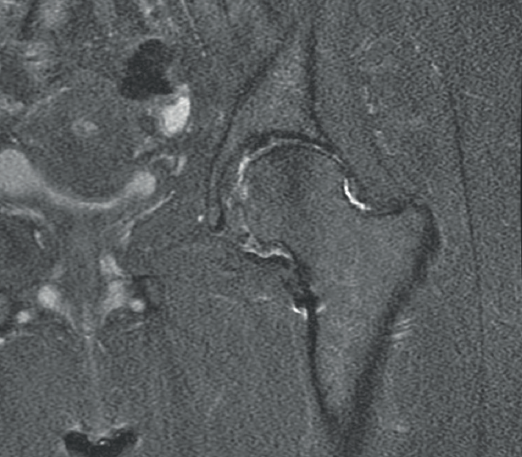

The postoperative radiographs (Figure 6) showed complete resection of the tumour, with correct joint congruence. The pathology findings were consistent with osteochondroma (Figure 7). The clinical course was favourable during the first year, with weight bearing using crutches for 6 weeks, followed by physiotherapy. The symptoms subsequently reappeared, with mechanical pain in the inguinal region that increased in intensity with rotation and caused limitation of her daily activities - the Harris Hip Score being 34 points out of 100. A new magnetic resonance imaging study revealed femoroacetabular impingement and thinning of the joint cartilage (Figure 8). A total hip arthroplasty was therefore proposed and carried out 18 months after arthroscopic resection of the osteochondroma. The femoral head was sent for histopathological study, which confirmed the existence of residual osteochondroma (Figure 9).